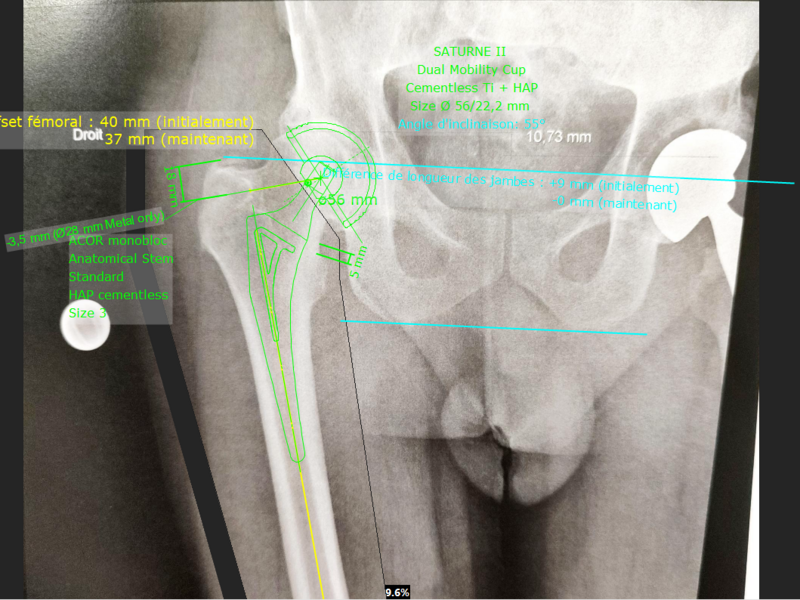

Album photo